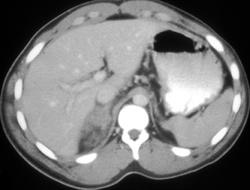

Renal Laceration and Rupture